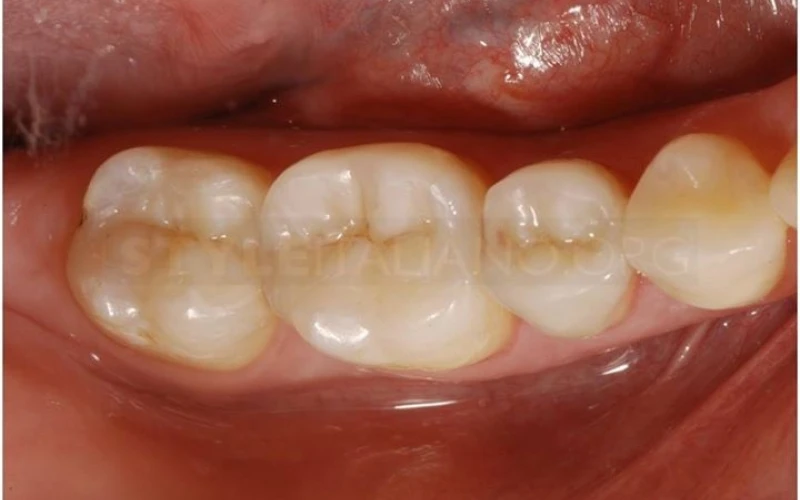

1. Khám ban đầu: Bệnh nhân phàn nàn về cơn đau xảy ra ở nhiều răng trên cùng một bán cung hàm.

12. Hình ảnh lâm sàng phục hình sau cùng.